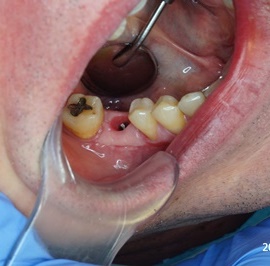

Odbudowa lewego dolnego trzonowca.

Odbudowa prawego dolnego trzonowca.

Uzupełnienie trzonowców: szóstki i siódemki na implantach.

Odbudowa kości, dziąsła, implantacja, korony protetyczne, dwa prawe dolne trzonowce.